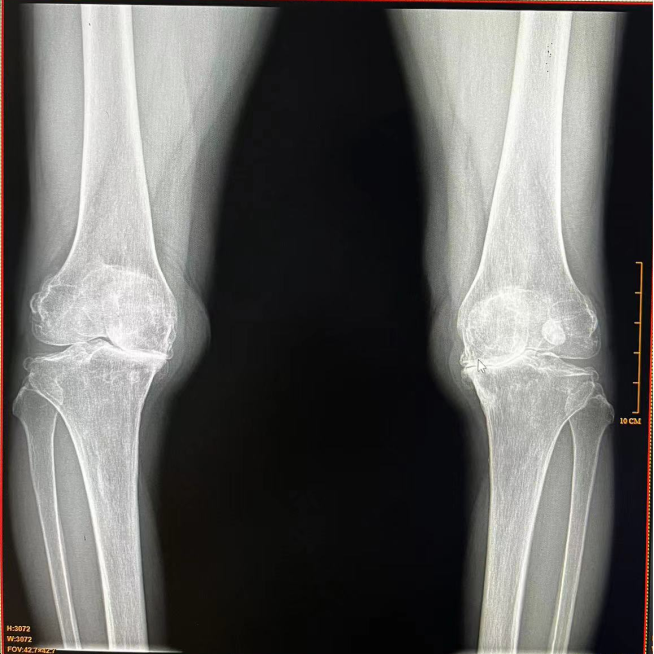

▲全膝关节表面置换术

人工膝关节置换技术是膝骨关节病终末期治疗的优选方法,是精确到毫米级的手术。它对人员的资质、手术室的各项标准、手术团队、以及相关科室和设备设施条件均有严格规范的要求。

膝关节单髁置换手术,顾名思义,就是仅对膝关节中的某一侧(内侧或外侧)进行置换,以恢复关节功能、减轻疼痛。与传统的全膝关节置换手术相比,单髁置换手术具有创伤小、恢复快、手术外表美观等优点。